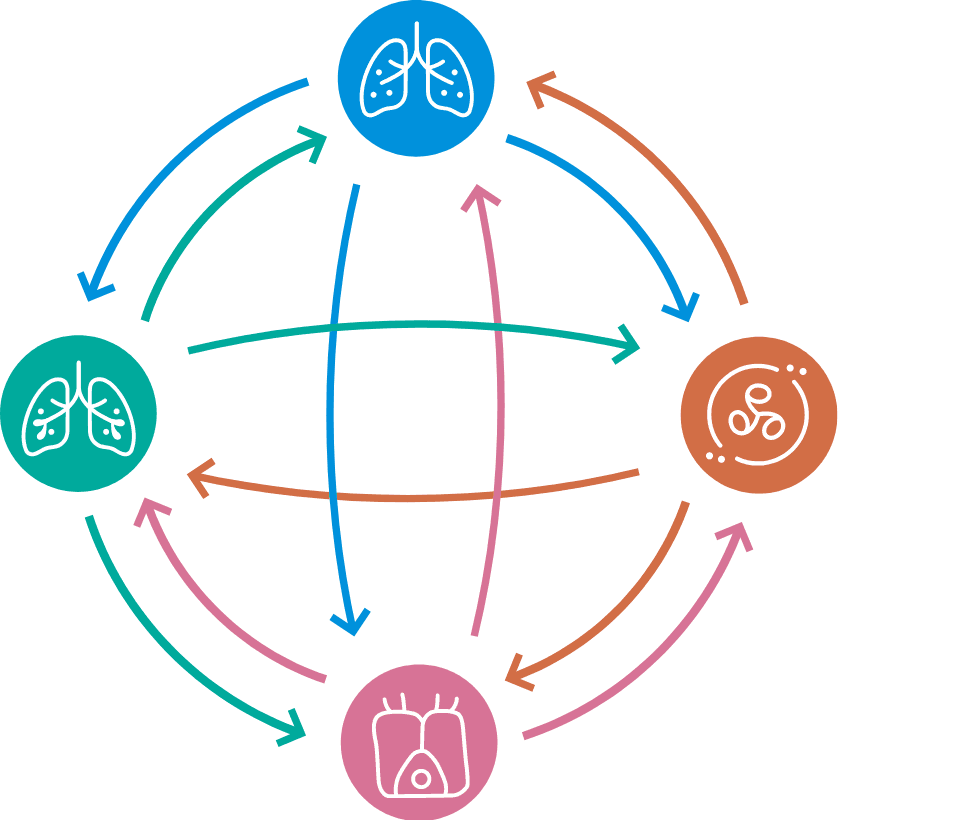

病態